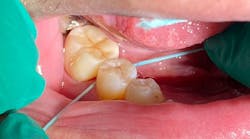

My fifth—and probably most important—tip is to invest in a computer-aided anesthetic device. Specifically, I use the Calaject from Directa Dental, which I’ve found to be the most versatile and cost-effective unit available. This device dispenses local anesthetic at a controlled flow rate, using the back pressure from the anesthetic to allow for precise and pain-free injection. Most of us know that the pain from an injection comes from adding liquid volume into a space that cannot expand to accommodate it. Calaject’s design follows scientific recommendations for the speed and pressure of anesthesia administration, ensuring a pain-free and comfortable experience for patients.

The Calaject system is designed to replace traditional injection techniques. It consists of three components: the main module with a long-lasting rechargeable battery and easy-to-clean control panel, a small foot pedal that connects to the main module, and a pen-shaped handpiece that eases anxiety by replacing the traditional dental syringe. The handpiece features a clear, autoclavable barrel that holds the anesthetic cartridge and needle, and it also has an auto-aspiration feature that prevents anesthetic from leaking where it’s not needed. The system offers three separate modes for intraligamental/palatal injections, infiltrations, and regional blocks, along with a prominently featured pressure gauge, which is critical for live feedback during PDL/palatal injections.